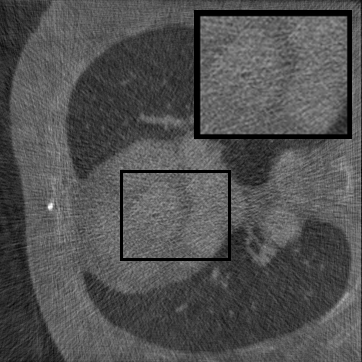

Figure 3: Qualitative completion results on TomoBank (lines 1 to 2) and LoDoPaB (lines 3 to 4) with random mask (ratio = 0.8) at 1024×\times1024 resolution. Odd columns and even columns show the sinograms and reconstructed images, respectively.

4.2.3 Completion Quality

Tab 2 summarizes accuracy results. At 2048×\times2048 resolution, HRSino achieves the best performance among all baselines while remaining memory-efficient, demonstrating its ability to extend high-quality completion to resolutions where other diffusion models fail. At 1024×\times1024, HRSino delivers accuracy comparable to its computation-intensive counterpart RePaint, showing that our optimizations do not compromise fidelity at moderate scales. Compared to DiffIR, MCG, TD-Paint, and HiDiffusion, HRSino consistently achieves higher SSIM and PSNR across mask ratios, with improvements up to +0.03 SSIM and +1.8 dB PSNR. Fig 3 visualizes sinogram completion and reconstructed images, where HRSino produces nearly indistinguishable results from RePaint. These findings confirm that HRSino fundamentally extends diffusion-based completion to 2048×\times2048 resolution in a more memory- and runtime-efficient manner.